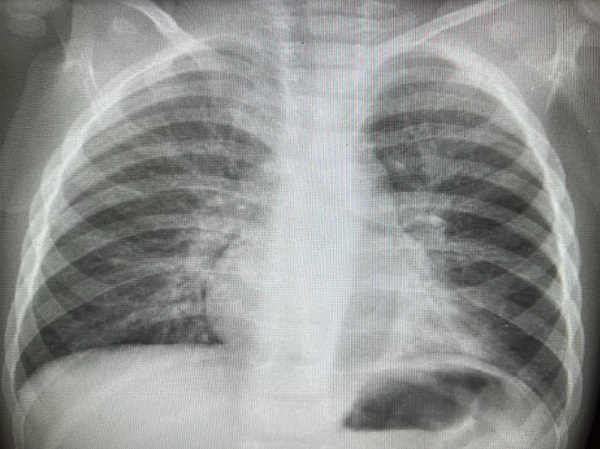

En el siguiente mes presenta nuevo episodio febril con imagen de neumonía atelectasia persistente en LII en la radiografía (Rx) (Figura 3).

Figura 3. Neumonía atelectasia persistente en LII